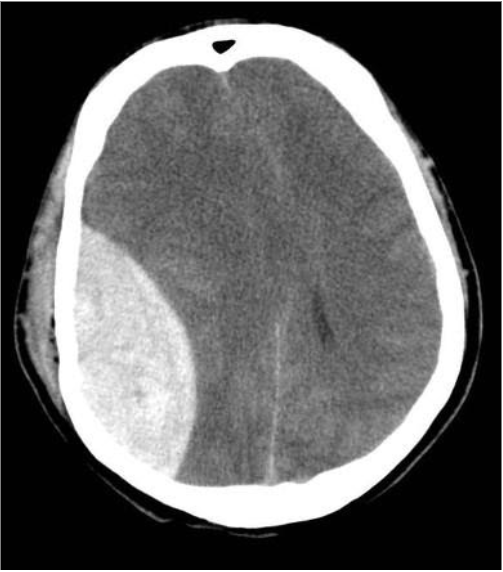

Questions 1-4 are based off the following two images:

Name the type of haemorrhage in each image.

Image 1: Subdural haemorrhage, Image 2: Extradural (Epidural) haemorrhage

Describe the shape of the haematoma in each image.

Image 1: Crescent, Image 2: Lentiform/Biconvex

What vessels are characteristically damaged in each image?

Image 1: Cortical bridging veins, Image 2: Middle meningeal artery

Other than shape and origin of bleed, what other characteristic distinguishes the above two bleeds from each other?

Subdural bleeds cross suture lines, extradural bleeds do not